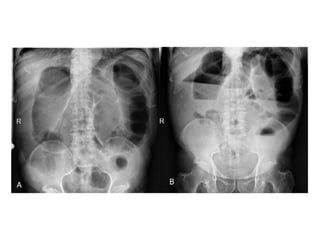

• La triada clásica de

obstrucción en el examen

radiológico es:

o Asas de intestino delgado dilatadas

(mayores a 3 cm)

o Niveles hidroaéreos

o Ausencia de aire distal

Signo del “grano de café”

Hallazgo clásico y diagnóstico del vólvulo sigmoideo en una radiografía simple de abdomen

El diagnóstico seconfirma mediante estudios radiológicos SERIE ABDOMINAL Rx abdomen paciente en posición supina Rx tórax Rx abdomen con enfermo de pie SENSIBILIDAD DEL 70 AL 80%

• La triadaclásica de obstrucción en el examen radiológico es: o Asas de intestino delgado dilatadas (mayores a 3 cm) o Niveles hidroaéreos o Ausencia de aire distal

Signo del “granode café” Hallazgo clásico y diagnóstico del vólvulo sigmoideo en una radiografía simple de abdomen